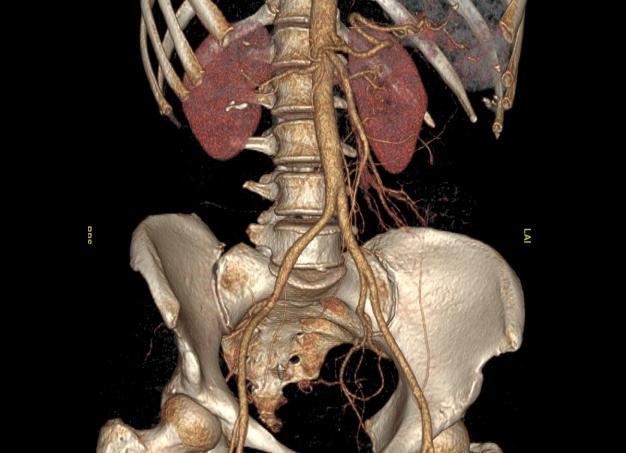

КТ органов грудной клетки называется исследование тканей и внутренних органов человека (в данном случае – области груди) посредством сканирования рентгеновским излучением. Благодаря своей высокой информативности, данный метод является очень востребованным при проведении диагностики болезней, способствуя выявлению с большой точностью аномалий, новообразований, травматических последствий и других нарушений в грудине, легких, пищеводе, дыхательных путях, кровеносных сосудах, плевре, молочных железах, лимфатических узлах, ребрах. Помимо этого, КТ оценивает месторасположение, структуру данных органов, в прямом смысле слова проливая свет на любую патологию тканей и органов, – даже на ранней стадии и протекающую в скрытой форме. Подробнее ...